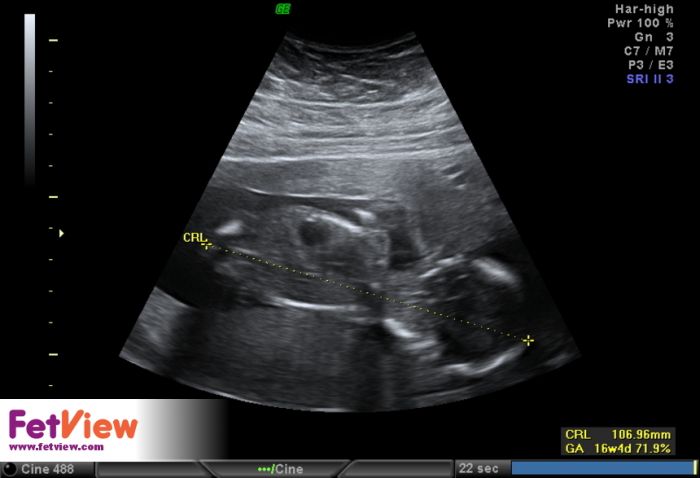

Tak se hlásím z kontroly na genetice a podrobný ultrazvuk vše vypadá v pořádku. Po odběru choriovych klku jse vše v pohodě. Žádný problém tam není. Miminko v pořádku i ten tok pupečníku je lepší po těch tabletkach. Tak jsem šťastná jen se nechtěla nechat vyfotit celá. Tak jen z prifilu